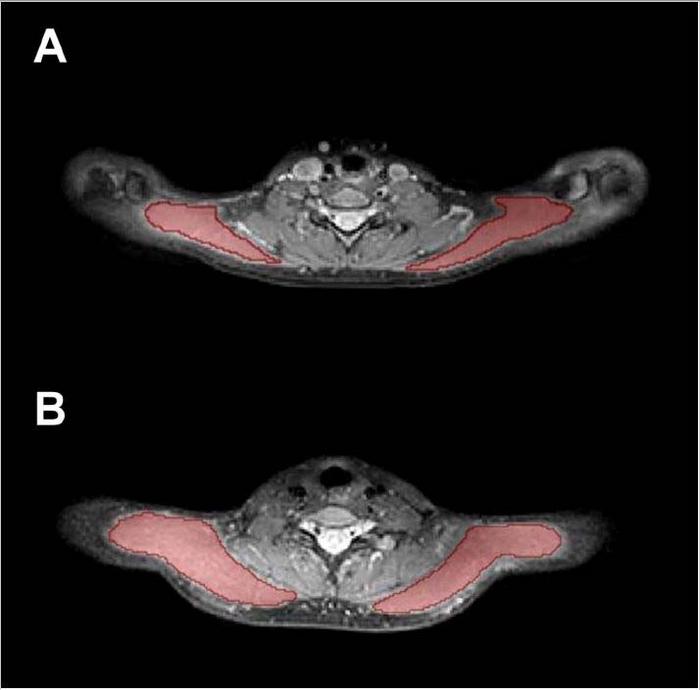

Exemplary cases for trapezius muscle segmentations.

EXEMPLARY CASES FOR TRAPEZIUS MUSCLE SEGMENTATIONS. (A) SEGMENTATION MASKS OF THE BILATERAL TRAPEZIUS MUSCLES (RED AREAS) IN A 25-YEAR-OLD FEMALE AND (B) IN A 24-YEAR-OLD MALE.

For the study, Dr. Sollmann and colleagues aimed to investigate the involvement of the trapezius muscles in primary headache disorders by quantitative magnetic resonance imaging (MRI) and to explore associations between muscle T2 values and headache and neck pain frequency.

All participants underwent 3D turbo spin-echo MRI. The bilateral trapezius muscles were manually segmented, followed by muscle T2 extraction. Associations between muscle T2 values and the presence of neck pain, number of days with headache, and number of myofascial trigger points as determined by manual palpation of the trapezius muscles were analyzed (adjusting for age, sex and body mass index).